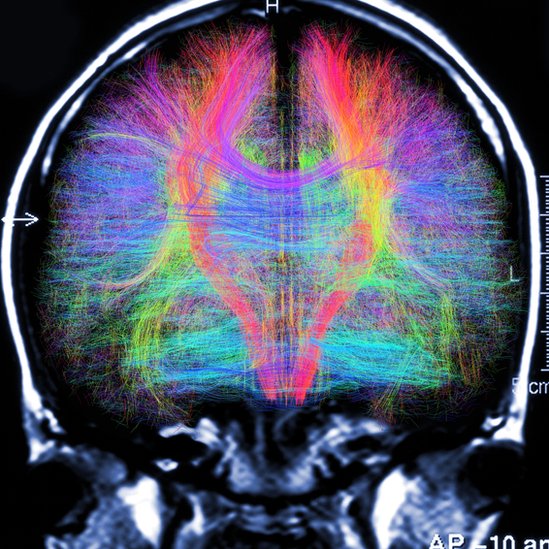

La investigación reveló que ese tipo de baile puede incluso aumentar la densidad de la llamada materia blanca, la parte del sistema nervioso central que coordina la comunicación entre las diferentes partes del cerebro.

La degeneración de la materia blanca en el cerebro, o desconexión estructural, es uno de los principales mecanismos neurológicos detrás del declive asociado al avance de la edad en funciones cognitivas como la velocidad para procesar datos, señala el estudio.

Y se les realizó un escáner cerebral con un tomógrafo de resonancia magnética.

Luego de seis meses, todos los participantes fueron sometidos nuevamente a pruebas y tomografías de resonancia magnética.

Aquellas personas que ya realizaban ejercicio antes del estudio fueron las que mostraron menor declive en su materia blanca, pero las que aprendieron las coreografías mostraron incluso un aumento en la materia blanca de acuerdo a las tomografías.

La materia blanca del fornix, una parte del cerebro relacionada con la velocidad de procesamiento y la memoria, mostró en el grupo de baile una mayor densidad que seis meses antes.